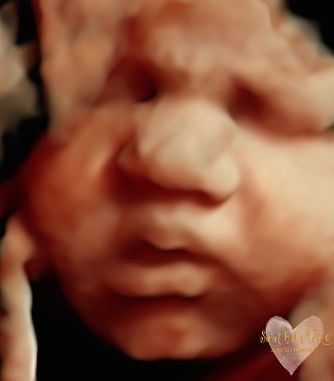

3D/4D/5D Ultrasound Gallery

Take a peek at our Photo Gallery. All of our 2D, 3D, 4D, HD elective ultrasound images are truly ours. They come directly off our machine from our highly trained staff. We can start getting great 3D/4D images as early as 10 weeks!